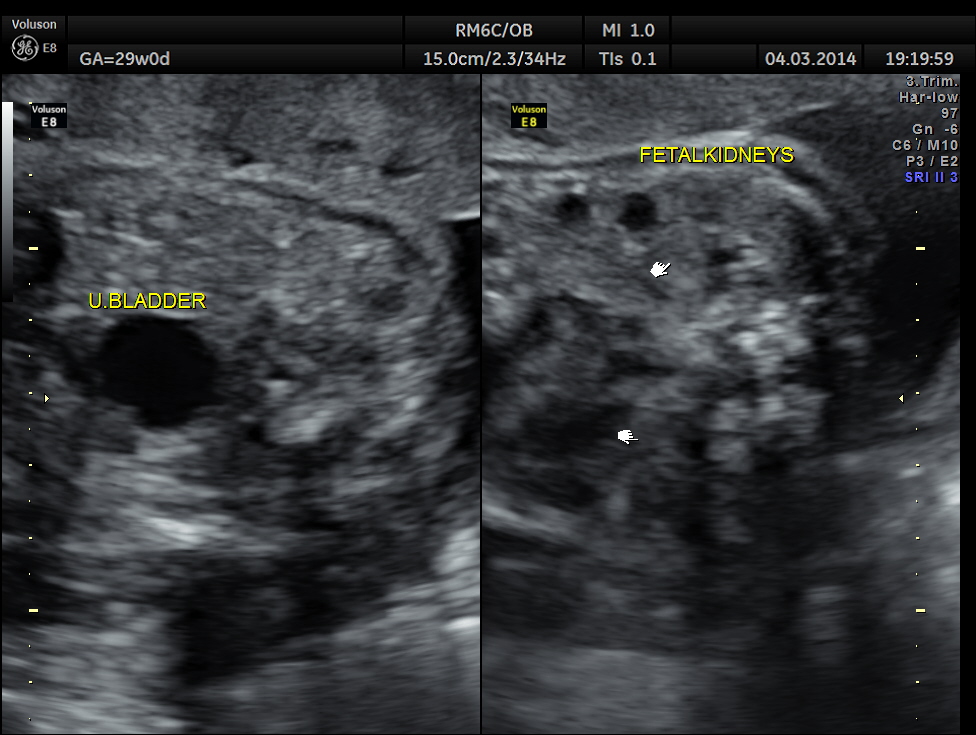

Images of the other organs are given below.